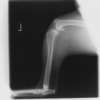

術後左後肢側面像

術後左後肢正面像

術前のTPAは左後肢33.1°右後肢26.8°でしたがTPLO実施により左後肢5.5°右後肢12°に矯正されました。